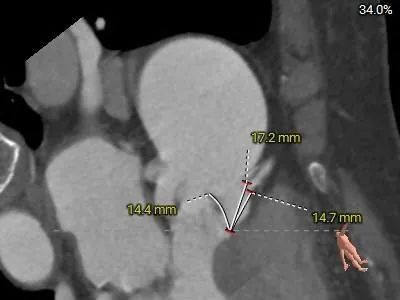

冠脉测量:

冠脉开口高度可,切线角度测量,未见冗长瓣叶